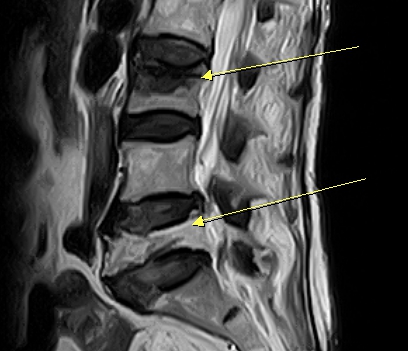

腰椎痠痛竟是壓迫性骨折,經採微創手術經皮椎體成形術,傷口小復原快,高齡長者術後當天可下床活動。圖/活力得脊椎外科提供

活力得中山脊椎外科醫院收治高齡阿嬤,院長楊椒喬指出,患者雖沒有跌倒或撞擊,但疼痛一直無法改善,除了走路疼痛之外,坐著休息時也痛,於是醫院安排她核磁共振檢查,發現患者在腰椎第3節及第5節有壓迫性骨折,考量婦人有兩處壓迫性骨折及超高齡,建議她接受灌漿治療。

楊椒喬指出,灌漿治療是「經皮椎體成形術」,利用影像引導,將穿刺針穿入壓迫性骨折的椎體,再注射骨水泥進入椎體,讓塌陷的椎體矯正與復位,並達到支撐椎體的目的;傷口不到1公分,而且縫1針即可,屬於微創手術。